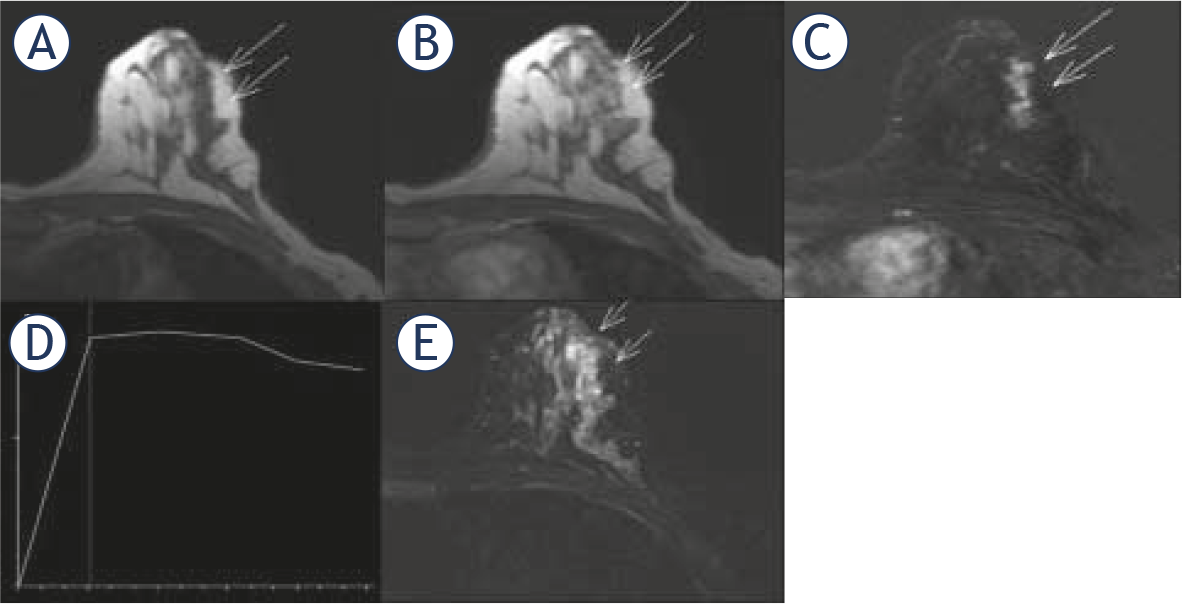

Nonproliferative lesion, proliferative lesions without atypia and proliferative lesions with atypia: dynamic contrast-enhanced magnetic resonance imaging (DCE-MRI) morphological and enhancement kinetics features, based on BI-RADS lexicon